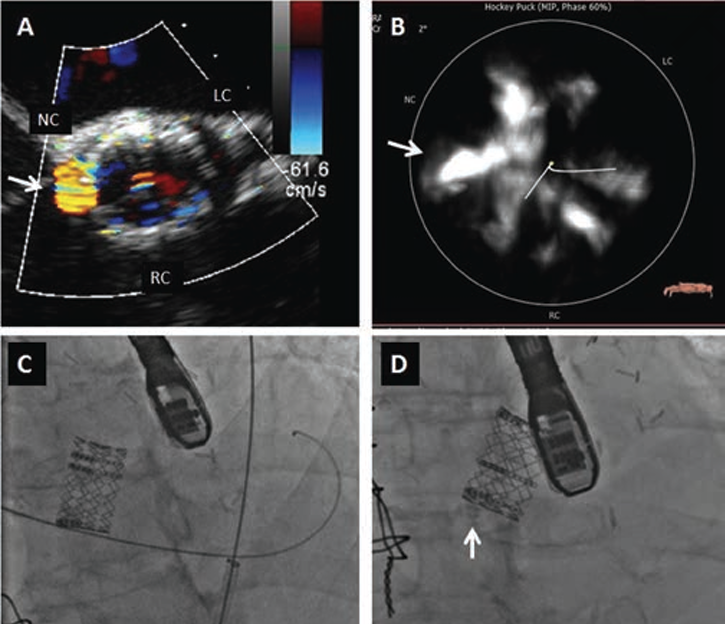

In 1 post-TAVR case, the patient received a transcatheter valve in a 23 mm Hancock II surgical prosthetic valve (Medtronic). The percutaneous PVL closure for this patient was successfully performed in the space between the surgical valve and TAVR valve (Figure 2). Another patient underwent TV-in-TV at 149 days after the index TAVR procedure because of worsening PVL; however, the PVL remained significant and the patient remained symptomatic. Percutaneous PVL closure was attempted 369 days after the index TAVR, but it was unsuccessful due to difficulty advancing the delivery sheath (Figure 3).

The etiology of PVL contributes to the procedure selection. There are several factors that have been considered as the etiology contributing to PVL after TAVR, ie, prosthesis underexpansion, undersizing, impingement of calcium nodules interfering with stent expansion, or incorrect positioning (too high or too low or not coaxial) leading to incomplete apposition of the valve skirt to the aortic annulus.10,16,17 Usually, balloon postdilatation using a slightly oversized balloon is the first option for PVL after TAVR. The use of this technique, however, is limited due to the possibility of damage to the prosthetic valve, prosthesis migration, aortic annulus rupture, or worsening central aortic regurgitation if present. TV-in-TV to treat this complication has also been described,4-6 but this technique may be less effective if the leak is produced by the presence of focal bulky calcium at the annulus, as was seen in 1 case of the present study wherein PVL was caused by calcification at the left coronary cusp; this patient underwent TV-in-TV at a later date post TAVR, but it was an unsuccessful procedure as previously described. The stent frame of the second valve might have been deformed by the focal calcification and contributed to the residual PVL (Figure 4). Percutaneous PVL closure should be considered for this focal PVL caused by calcification. Martinez et al proposed an algorithm for the percutaneous management of PVL in which repeat ballooning was the first option; if PVL persists, then another procedure should be considered based on the PVL shape (either TV-in-TV for circumferential PVL or percutaneous PVL closure with a closure device for focal PVL).6

Although percutaneous PVL closure definitely has a role in the TAVR era, it seems to be more challenging compared with the post-SAVR patients in our study. During TAVR, the irregular surface of the native calcified aortic valve leaflets are compressed between the wall of the aortic root and the expanded prosthetic valve stent frame. This creates resistance, and the occluder sheath and device are not able to cross an eccentric space between the calcified native leaflet and the stent of the valve. This hypothesis is supported by our observation that we had problems in advancing delivery catheters in all unsuccessful cases, although wires initially did cross. Moreover, the calcium burden of the corresponding leaflets was greater in these cases (351.4 ± 205.1 mm3 in unsuccessful cases vs 121.8 ± 111.7 mm3 in successful cases; P=.049), as demonstrated in Figure 4. This is in contrast to the post-SAVR group, in which all percutaneous PVL closures were performed successfully. The SAVR procedure removes the native leaflet, and the PVL site is therefore a much smoother surface.